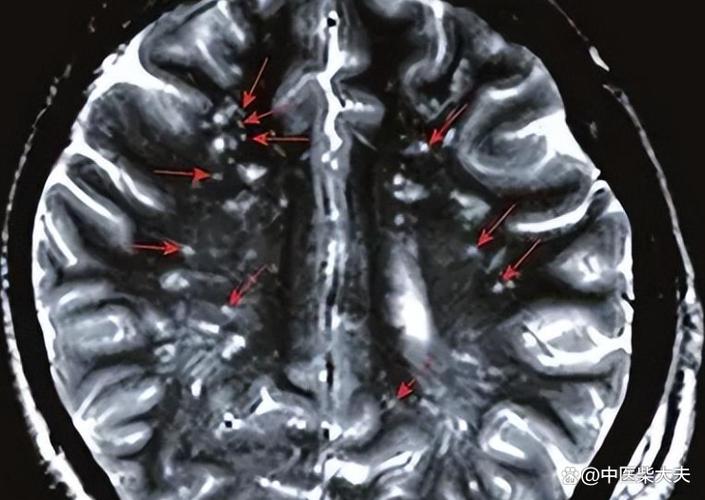

“缺血灶”和“脑腔梗”都是脑组织曾经缺血坏死的“遗迹”或“疤痕”,它们在核磁共振(MRI)上表现为信号异常的区域,是医生判断脑血管健康状况的重要依据。

缺血灶是一个比较宽泛的术语,可以把它理解为大脑某个区域曾经发生过缺血事件,并留下了一个“印记”,这个印记在影像学上表现为一个边界不清、形态不规则的异常信号区。

腔隙性脑梗塞是缺血灶中一个特定类型,有非常明确的定义和特征。

- 位置:发生在大脑半球深部、脑干等部位,这些区域的血管比较细长,被称为“穿通动脉”或“终末动脉”。

- 大小:病灶非常小,直径通常在 5毫米到20毫米 之间。

- 形态:病灶形态相对规则,呈圆形或卵圆形,像个小“豆子”或“小坑”。